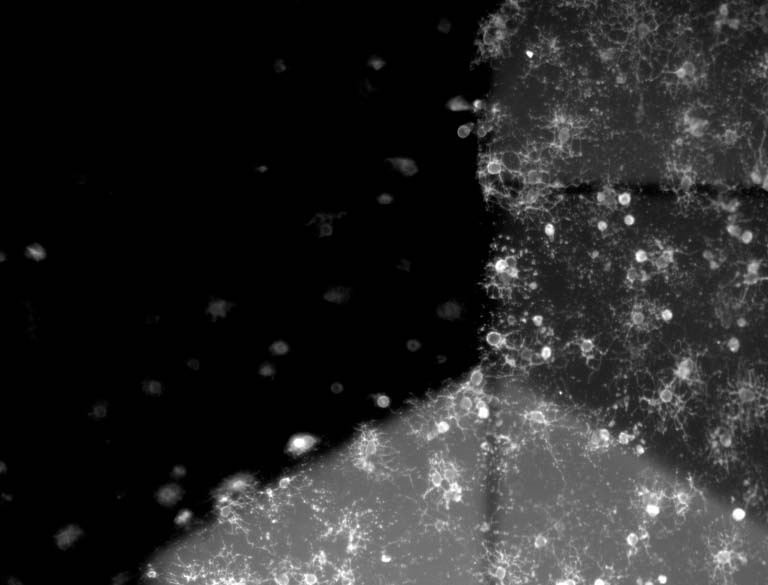

This image collection depicts the use of biocompatible 3D-printed materials to study the process of myelination, or wrapping of membranes around neuronal axons in the central nervous system, by oligodendrocyte cells. The process of myelination is involved in a myriad of disorders for which no therapies have been successfully developed. Understanding causes and potential treatments of disorders characterized by incomplete myelin production or myelin degeneration are particularly challenging due to a lack of predictive preclinical tools. Using these Artificial Axons, we can stimulate and quantify oligodendrocyte myelination in a well-defined environment that recapitulates key physical, mechanical and chemical properties of central nervous cells and tissues.